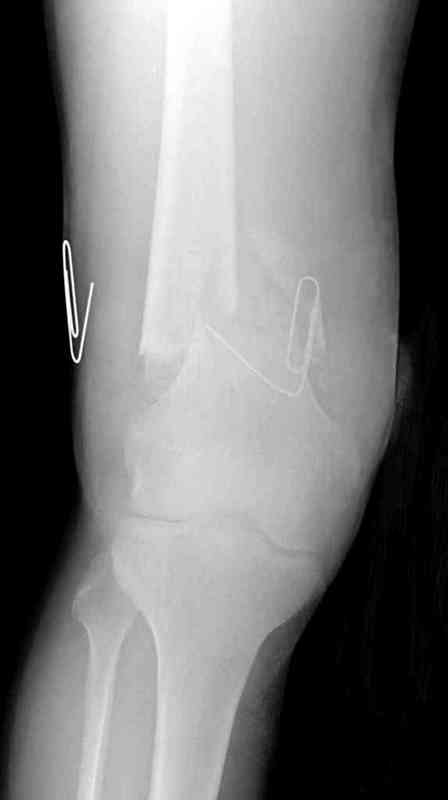

Пострадавшему 23, пистолетная огнестрельная не кроветочащая рана, меньше одного см диаметром, входное отверстие расположено латерально, и выход передне-медиально, и еще имеется второе пулевое ранение правой navicular bone с этой стороны.

Несмотря на сниженный до 0.9 BI-ankle-brachial-index (обязательное, недорогое исследование при подозрении на повреждение сосудов, рассчитанный по разнице давления в нижней и верхней конечности), последующее КТ ангиограмма не подтвердила повреждения артериальных сосудов.

Доступ был латеральный, при вскрытии с задней

поверхности бедра обнаружили кровотечение. Поднятием давления на заранее установленном турникете на конечности проконтролировали кровотечение.

В данном случае мы не ставили осуществление гемостаза приоритетным, после 30 минут больной оставлен вызванному сосудистому хирургу со стабильной фиксацией бедра. Несмотря на выбранный передне-медиальный доступ, хирург произвел восстановление сосудистого повреждения.

При близости сосудов к многооскольчатому повреждению костей, сперва необходимо удостовериться в наличии повреждения сосудов без применения турникета.

Сосудистые повреждения часто приводят к увеличению

давления в компартментах, мониторинг на голени показал увеличение, и поэтому сделана профилактическая латеральная фасциотомия.

Латерально пластину защитили ушиванием

илио-тибиального тракта, а медиальная сторона была ушита мышцей, и все раны закрыли ваккумированием (VAC)

На третий день после Irrigation & Debridment закрыли все раны за исключением компартментальной раны из-за отека, медиально в дефект кости установили Putty Grafton Bone Substitute. На компартментальную рану вакуум и мероприятия по сближению краев раны резиновой стяжкой.

На 9й день с момента травмы ушили рану без натяжения. Больной получает реабилитацию, движения коленного сустава с помощи CPM-continuous passive motion machine. Сегодня выписан.